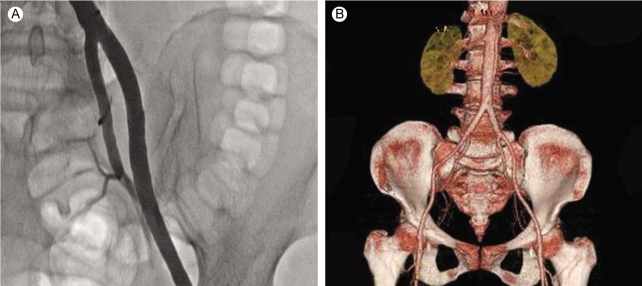

Computed tomographic (CT) angiography of the left lower extremity showed total occlusion of the proximal left common iliac artery (Fig. 1). Initially, we performed intra-arterial thrombolysis with urokinase 200,000 units for 1 hour. Follow-up angiography revealed antegrade flow with large residual thrombi (Fig. 2), so we decided to perform a percutaneous mechanical thrombectomy through the ipsilateral femoral artery using the OASIS™ thrombectomy system (Medi-Tech/Boston Scientific, Watertown, MA) (Fig. 3). Immediate post-procedural angiography demonstrated almost complete patency of the previously occluded artery. Follow-up CT angiography 14 days later showed a normal left common iliac artery (Fig. 4).